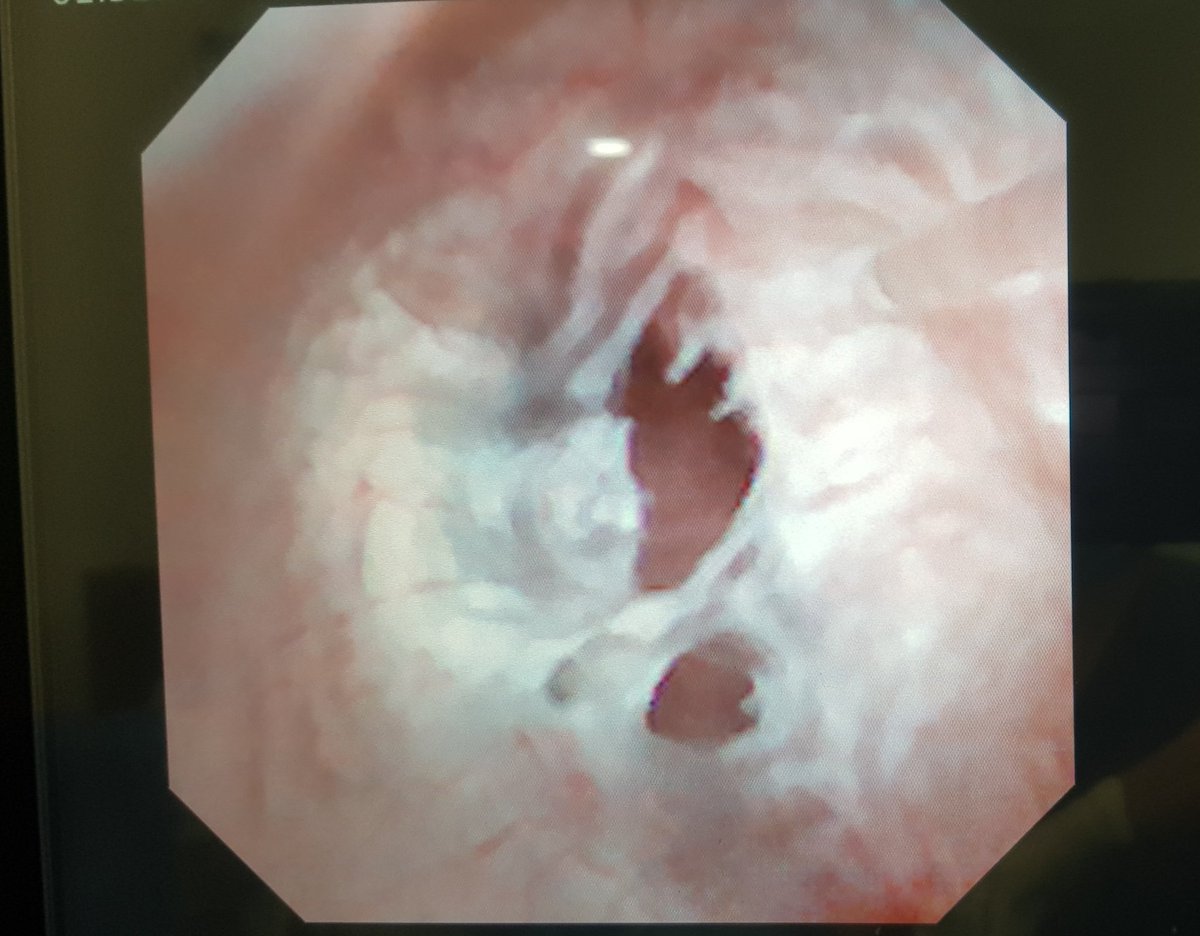

Enucleacion de

#Mioma uterino por#Histeroscopia con láser de#Holmium por el Dr. Jose Alanis en el@hospitalangeles del Carmen en el curso de Cirugía de Mínima invasión y Puerto Único#Guadalajarapic.twitter.com/A1oONbII9q -